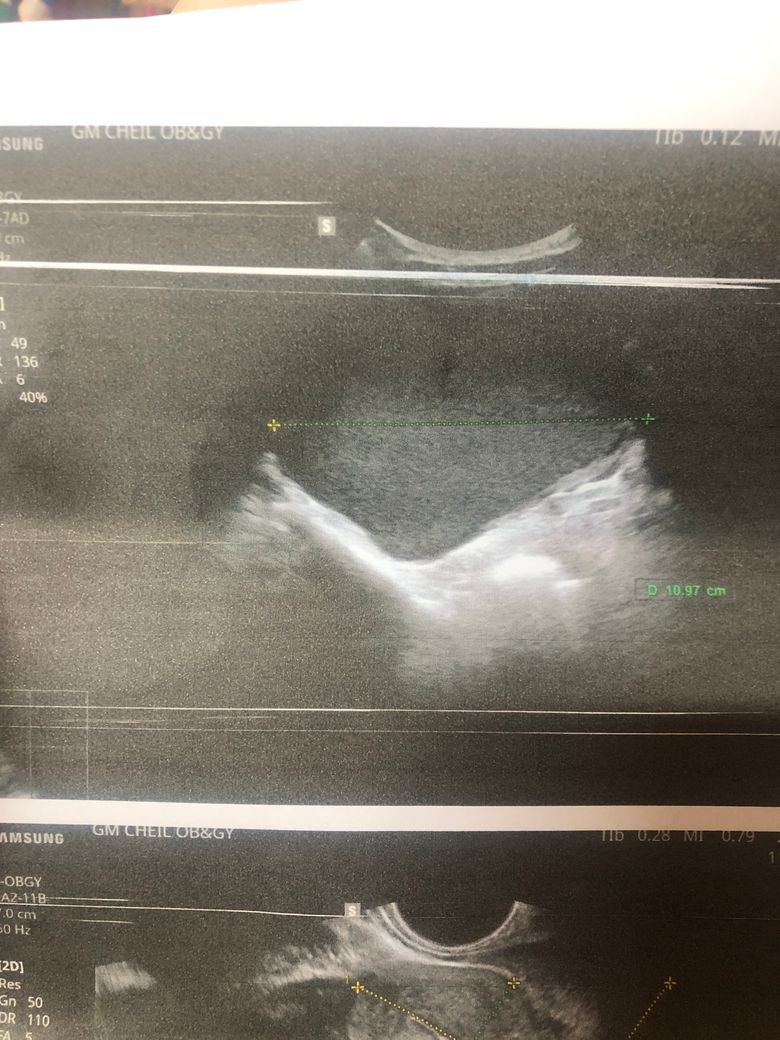

산부인과 검사 했는데요 혹이 있다고 해서 수술해야 한다고 하는데 꼭 수술밖에 답이 없나요?ㅠ(자궁쪽은 아닌거 같고 어디에 난 혹인지 정확히 모르겠다고 합니다)

• 2번 째 사진

• 골반 내부의 혹이 11cm나 된다면 크기가 매우 큰 것입니다. 현실적으로 수술적으로 제거하는 것이 가장 합리적이고 적절한 판단으로 보입니다만, 정확한 것은 큰 병원에서 추가적으로 정밀 검사를 하고 자세하게 파악한 뒤 새롭게 판단 받으시는 것이 좋겠습니다.